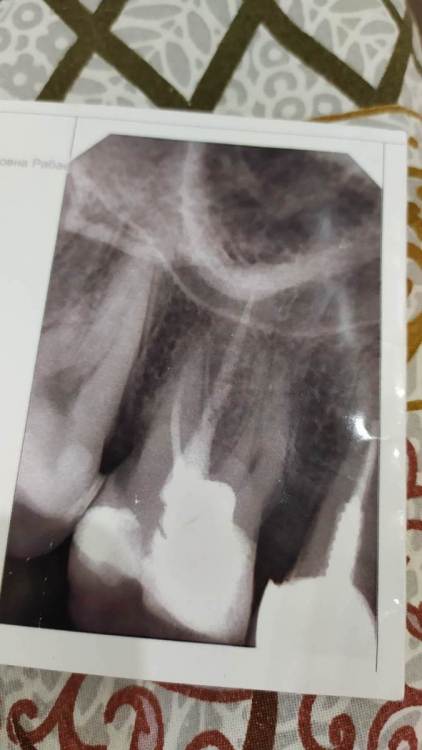

Рабин Опубликовано 31 марта, 2021 Поделиться Опубликовано 31 марта, 2021 Дорогие врачи, подскажите советом и есть ли вина ортопеда после постановки коронок. Неделю назад ставила 2 коронки на 5 и 6 верхние зубы. Примерно через 4 дня на десне над 6 зубом образовался свищ. Хирург на осмотре определил, что это киста и вычистил её кюретажом десны (за мои деньги) До этого 6 зуб был пролечен, каналы и т. д, но до одного корня невозможно было добраться, лечили его давно. Я специально понаблюдала за зубом в течение 2 месяцев, перед тем как ставить коронку на этот 6 проблемный зуб. Все было отлично! Но вот после того как ортопед поставил коронки выскочила эта киста на зубе. Совпадение? Скажите, может ли из-за некорректного протезирования, образоваться киста на зубе? 15 лет зуб этот не беспокоил, даже с непроходимым каналом... Дело в том, что ортопед работал без перчаток, при обточке зуба под коронку было много крови... Естественно десна воспалилась... Прилагаю фото рентгена. Скажите, чем грозит мне в будущем зуб, если на нём прочистил хирург кисту. И нужно ли снимать свежую коронку? И смотреть что там с зубом внутри и не подлежит ли он удалению? Гарантия на эти коронки у меня год. Ортопед предлагает ходить с ней дальше, если не заболит. Спасибо за ответы заранее. Очень переживаю за эту ситуацию и не вылезаю уже из больницы после протезирования. Скажите правильно ли поставлены коронки и пролечены каналы у 6 зуба? Скрытый текст Ссылка на комментарий

Рабин Опубликовано 1 апреля, 2021 Автор Поделиться Опубликовано 1 апреля, 2021 4 часа назад, chervoncevdaniil сказал: Ортопед своими действиями занести туда обострение не мог,это произошло потому,что у вас непролечен канал и вы судя по всему осознанно шли на этот риск. Вылечить "кисту"без пломбировки корневого канала невозможно,потому что там сейчас целый канал с инфекцией,которая никуда не денется,просто обострения могут со временем стихать и заново повторяться Спасибо за ответ! Скажите, если не снимать коронку, как предлагает ортопед, может ли киста пойти и на соседний 5 зуб? И скажите, видите ли вы воспаление на данных снимках? Я пошла на это осознанно, так как все врачи твердили, что у меня нет на зубе воспаления, корни хорошие, можно ставить коронку, несмотря на то, что один канал резорцирован. Он меня ранее 10 лет не беспокоил. Спасибо! Ссылка на комментарий